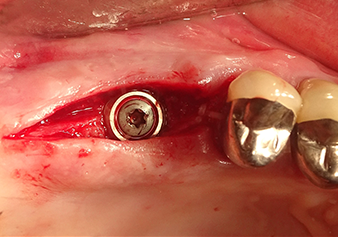

Implantation et restauration prothétique

Pour mettre en place le matériau d’augmentation en douceur en direction du sinus maxillaire, l’implant est inséré manuellement très lentement (Fig. 9). Pendant l’opération, la membrane est poussée de nouveau dans la direction crânienne. Au bout de deux mois, le site chirurgical cicatrise sans signes d’irritation. Six mois plus tard, la radio de contrôle révèle une augmentation significative de l'opacité indicative de l’ossification (Fig. 10). La restauration prothétique est réalisée avec une couronne métallo-céramique.